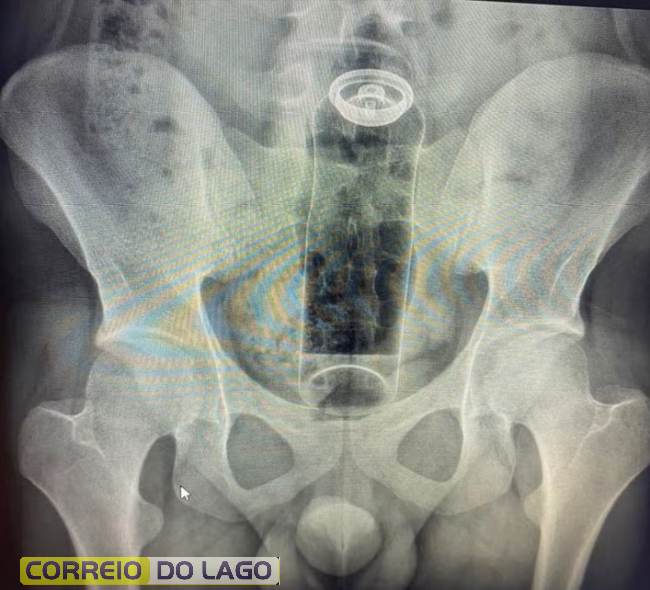

Paciente é internado após ficar com desodorante preso no reto; médicos fazem alerta

Especialistas explicam que objetos não apropriados podem causar perfurações, infecções graves e até levar à morte.

Seja por curiosidade, para apimentar a relação ou para experimentar a própria sexualidade, há quem goste de explorar o prazer na região anal na “hora h”. Especialistas explicam, no entanto, que é preciso cuidado com o que é introduzido. Um médico usou as redes sociais para fazer o alerta depois de atender um jovem que precisou ser internado para retirar um desodorante do reto.

De acordo com o médico Daniel Brosco, cirurgião coloproctologista, o paciente tinha 19 anos e contou que colocou o desodorante no ânus durante uma “brincadeira” sexual. A embalagem, porém, acabou subindo para o reto e não conseguiu ser retirada em casa. (Veja a imagem abaixo)